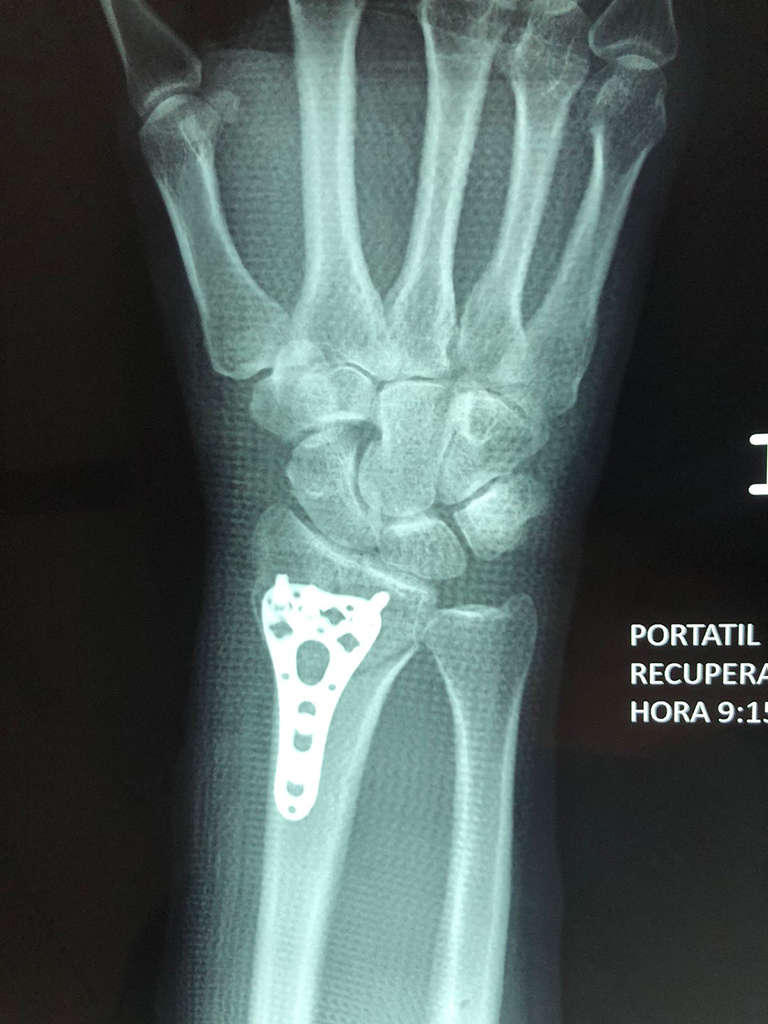

Cirugías de Codo - Cirugías de Muñecas y Manos

Los procedimientos más comunes en cirugía de la mano son aquellos destinados a reparar traumatismos, incluyendo lesiones de tendones, nervios, vasos sanguíneos, y articulaciones; huesos fracturados; y quemaduras, cortes, y otros daños de la piel.